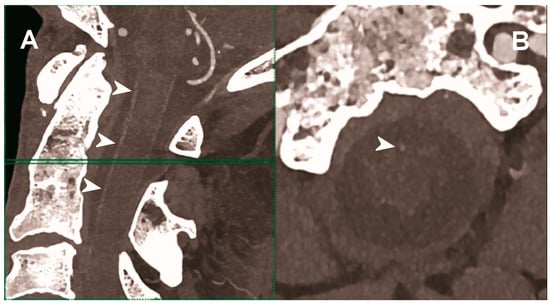

Figure 5.

Carotid CT angiography using photon-counting computed tomography. The figure shows advanced MIP reconstructions of a intracervical artery tree derived from a photo-counting CT (Scanner: NAEOTOM Alpha, Siemens) acquisition. In (A) a sagittal median view of the cervical region showing the course of the anterior spinal artery (normally not visible) in the ventral portion of the rachidial channel (arrowheads). In (B) the axial image at the level of the green plane showed on the left panel with the axial view of the anterior spinal artery (arrowhead).

The capability of PCCT technology to improve carotid and intracranial angiography has been demonstrated in vivo in a pilot study involving 16 asymptomatic subjects [49]. Compared to conventional CT, PCCT offered less image noise (9%) and beam-hardening artifacts in internal carotids close to the surrounding bone. Accordingly, the two radiologists blinded to the detector subsystem attributed to the images obtained with PCCT significantly higher quality scores for all vascular segments. Finally, the above-mentioned study showed the feasibility of spectral material decomposition of PCCT in the neck and brain for vascular imaging, although a direct comparison of the spectral performance between PCD and comparable dual energy EID CT scanners was not performed.